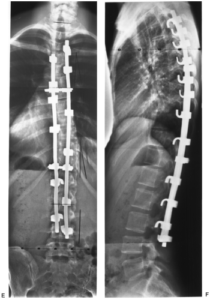

Когда удаляют полностью диск, нередко в освобожденную межпозвонковую полость помещают имплантат, скрепив позвонковую пару стабилизирующей системой. В позвоночник вставлены титановые болты для прочной фиксации поперечного стабилизатора, который в свою очередь будет отвечать за правильное положение относительно хребтовой оси смежных костных тел. Вкручивание болтов осуществляется через дужку в тела позвонков. Современная металлоконструкция обычно представлена динамическими болтами, что позволяет сохранить подвижность прооперированного уровня, максимально приближенную к норме.

Пример такой операции на рентгене.

Фиксация поясничного отдела при помощи металлоконструкции.

Последствия после операции c фиксацией шурупами по большей мере люди характеризуют так: выраженная блокада двигательных функций спины. Это явление чаще носит временный характер, поэтому далеко не всегда речь идет об осложнениях. К концу реабилитации, выполненной на безупречном уровне, амплитуда движений и гибкость позвоночника с металлоконструкцией восстановятся до максимально возможных значений. На адаптацию уходит приблизительно 6 месяцев. Среди истинных последствий после вживления имплантатов с шурупами выделяют высокую предрасположенность к появлению прогрессирующего дегенеративного патогенеза на соседних со стабилизированной частью уровнях.